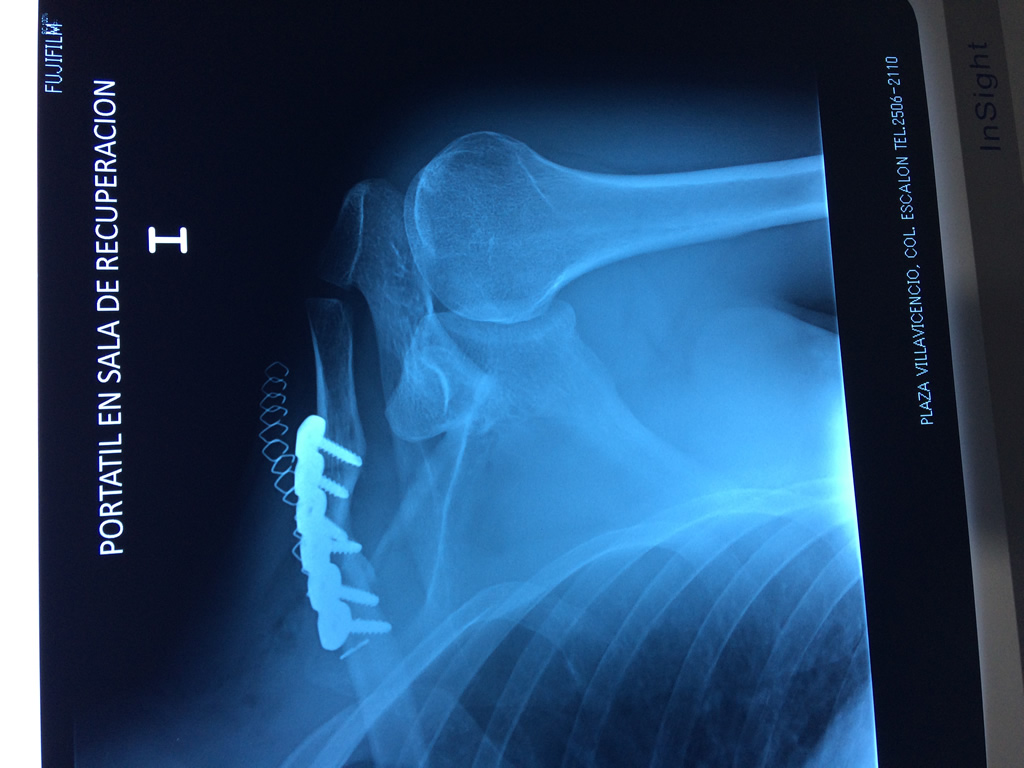

Cirugías de Codos - Clavícula

La clavícula es un hueso largo, con forma de "S" itálica, situado en la parte anterosuperior del tórax. Junto con la escápula forman la cintura escapular. Se puede palpar por toda su longitud y se extiende del esternón al acromion de la escápula, siguiendo una dirección oblicua lateral y posterior.

Se considera el único medio de unión entre el miembro superior y el tórax. A pesar de su aspecto, similar al de un hueso largo, posee una estructura semejante a la de un hueso plano, ya que carece de epífisis y de diáfisis, lo que la harían entrar dentro de la clasificación de hueso largo. Carece de un canal medular propiamente dicho.